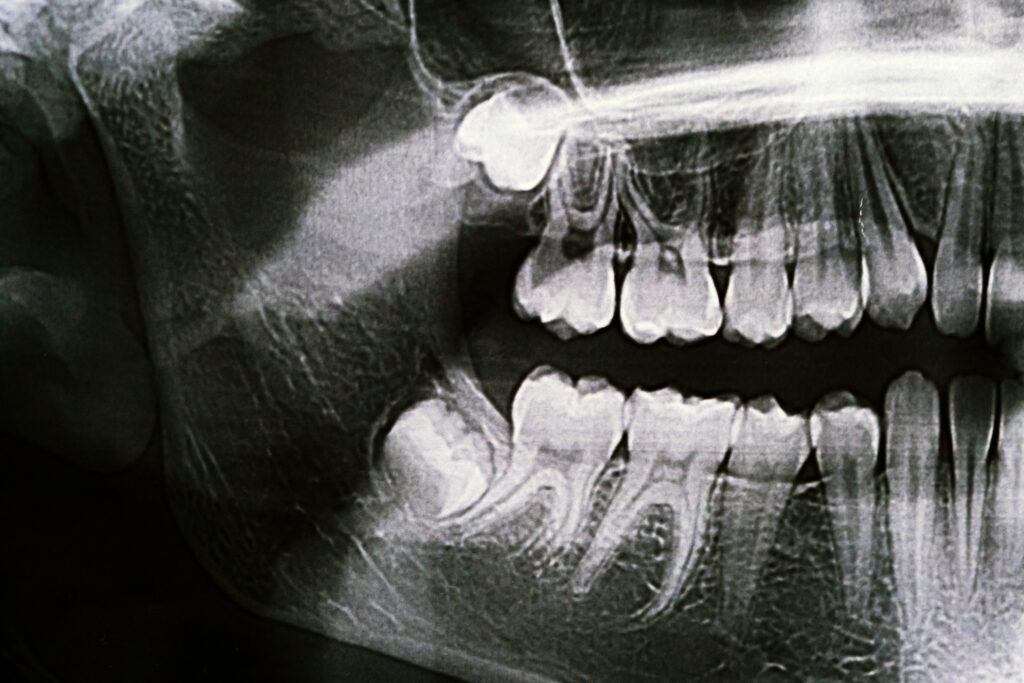

Diş implantı, kaybolan dişlerin yerine yapılan titanyumdan yapılmış vida şeklindeki yapay diş kökleridir. İmplantlar, çene kemiğine yerleştirilir ve üzerine protez dişler yerleştirilerek, doğal dişlerinize benzer bir görünüm ve işlevsellik sağlanır. İmplantlar, sadece estetik değil, aynı zamanda çiğneme fonksiyonunu geri kazandırarak, yaşam kalitesini artırır.

• İmplantın Yerleştirilmesi: İlk aşamada, implant yerleştirilecek çene kemiği hazırlık yapılır ve titanyum vida (implant) kemiğe yerleştirilir. Bu işlem genellikle lokal anestezi altında yapılır.

• İyileşme Süreci: İmplant yerleştirildikten sonra, çene kemiği ve implant arasında kaynaşma süreci başlar. Bu süre birkaç ay sürebilir ve bu süre zarfında, implantın kökleri tamamen çene kemiğine entegre olur.

• Protez Dişin Yerleştirilmesi: İmplantın tam olarak kaynaşmasının ardından, üzerine diş yapısına uygun bir protez diş yerleştirilir. Bu diş, doğal diş gibi görünür ve fonksiyonel olarak çalışır.